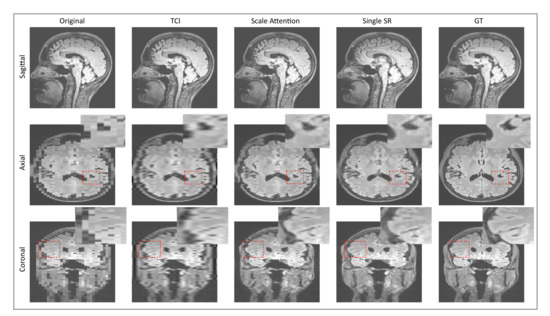

3.2. Single-Scale and Scale-Attention Model Comparison

The SR technique shows its potential as a better “interpolation”, given the active demand for data augmentation in medical-imaging deep-learning tasks. The feasibility of this idea requires an adaptive SR model which is designed to incorporate random sampling factors. Figure 2a compares the single-scale SR model with our scale-attention SR model at a sampling factor equal to 5. We can imagine that, to some extent, the scale-attention model must sacrifice partial resolutions, as a trade-off for allowing arbitrary scale entries. However, the images obtained by the scale-attention model are still of satisfactory quality compared to the tricubic interpolation (TCI) and single-scale model.

Figure 2.

(a) Comparison between single-scale model and scale-attention model on T1-weighted brain MRI. The figure shows original slices, cubic interpolation and ground-truth slices as a reference. Residual images at higher contrast are added to better visualize the difference of the generated images to the ground-truths. (b) Quantitative comparisons of measures: (b-i) RMSE, (b-ii) PSNR, and (b-iii) SSIM in terms of the sampling factor s between the single-scale model, the scale-attention model, 3D perceptual GAN (SOUP), and cubic interpolation. Statistical significance is indicated on the x-axes with * for and ** for . TCI: tricubic interpolation; GT: ground truth.